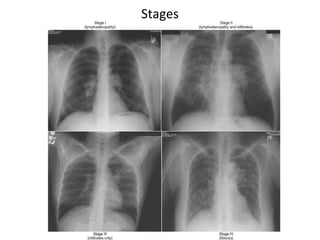

4 Stages of Pulmonary Sarcoidosis

I Bilateral hilar lymphadenopathy

and paratracheal adenopathy

55-90%

remission

II Mediastinal adenopathy with

pulmonary parenchymal

involvements

40-70%

III Pulmonary parenchymal without

adenopathy

10-20%

IV Pulmonary fibrosis with

honeycombing

0-5%

4 Stages ofPulmonary Sarcoidosis I Bilateral hilar lymphadenopathy and paratracheal adenopathy 55-90% remission II Mediastinal adenopathy with pulmonary parenchymal involvements 40-70% III Pulmonary parenchymal without adenopathy 10-20% IV Pulmonary fibrosis with honeycombing 0-5%